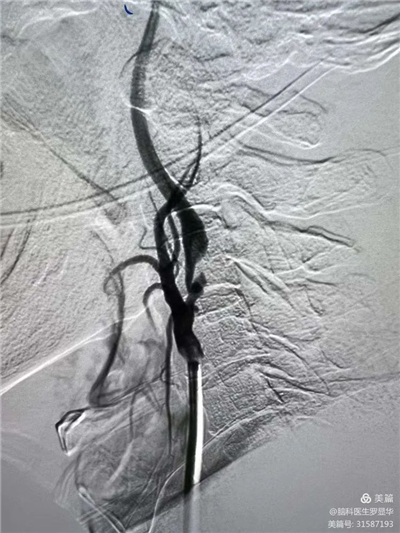

李東波副院長團隊正在為患者行頸動脈支架植入術(shù)

手術(shù)過程:指引導(dǎo)管到位

手術(shù)過程:球囊擴張后,protege支架到位

術(shù)后造影示狹窄解除